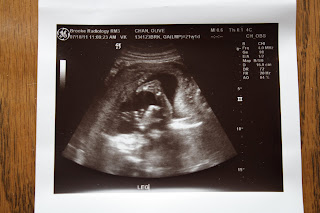

We had our first ultrasound this morning – what they call a “dating ultrasound”, to confirm the age of the baby. And yes, there is only one baby in there!

I’m officially at 15 weeks and 1 day, which means my new due date is December 1st. During our ultrasound, we could see the baby’s little heart beating away and we saw him/her wave his/her arms and kick his/her legs. I can’t feel any of the movement yet, but it was so neat to see it all.

T was a little panicked because he had trouble finding parking and I was already in the examination room by the time he arrived at the clinic. Thankfully, the technician had to do her thing first before allowing the both of us to see it. So in the end, we both got to see the first glimpses of our baby.